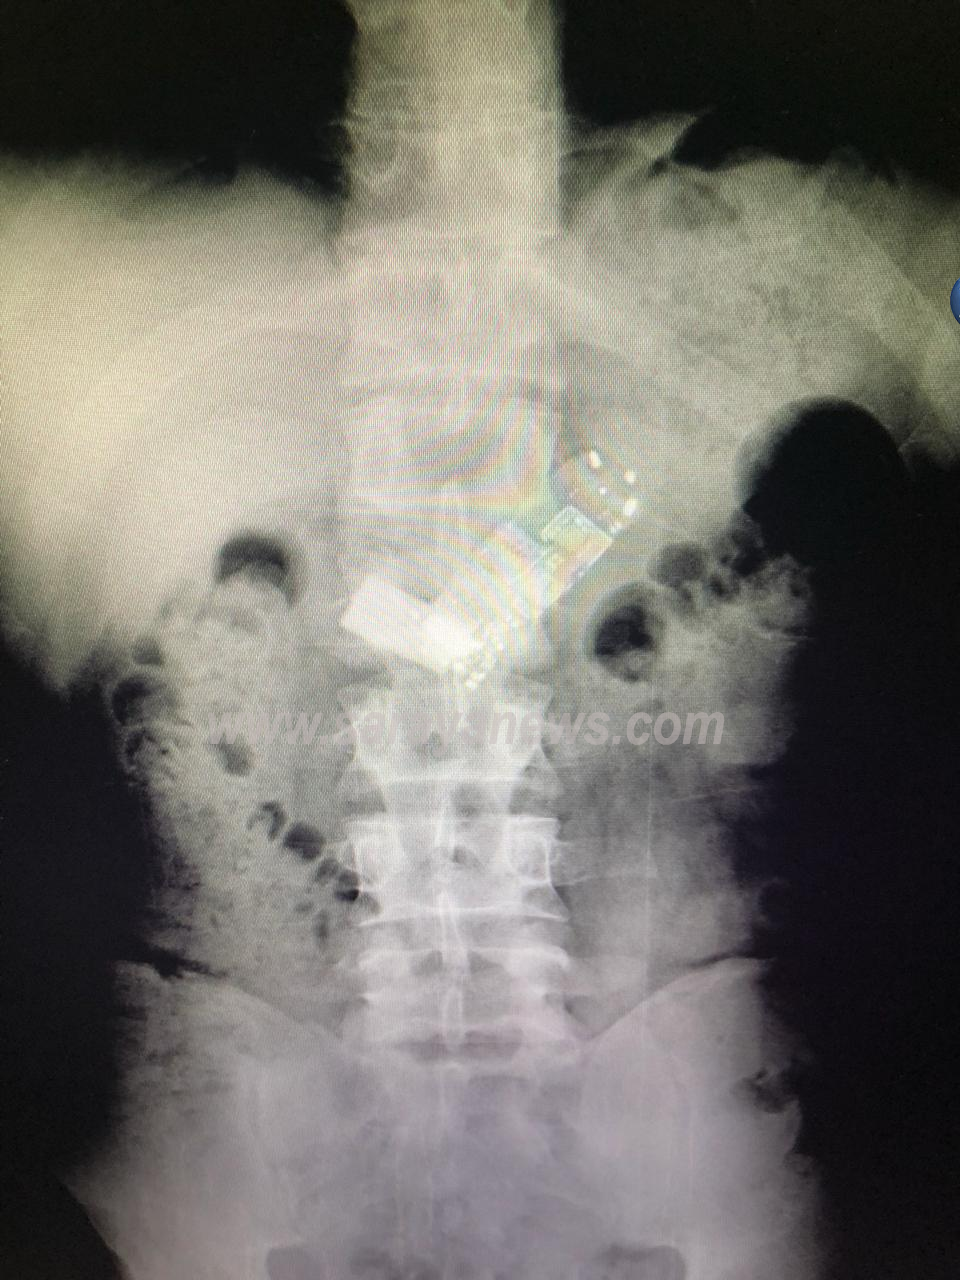

واضاف المصدر لسرايا ؛ انه وبعد تصوير المريض لتشخيص حالته ، تبين وجود هاتف نقال كان قد ابتلعه المريض ، وتم ادخاله الى غرفة العمليات مباشرة.

ولفت المصدر ، انه تم استدعاء رئيس قسم الجراحة الدكتور نايف العبدللات وفريقه الجراحي لمحاولة استخراج الهاتف ، حيث تم اجراء عملية جراحية لاستخراج الهاتف بعد فشل عملية التنظير.